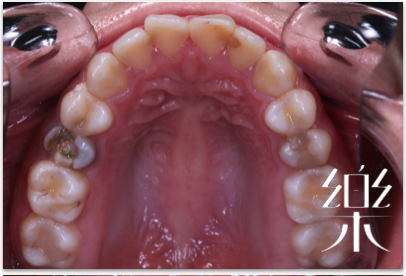

舌側隱形矯正器案例

病患在意牙齒暴牙,以及覺得嘴唇比較外突,也希望能改善看起來不健康漂亮的牙齒,藉由朋友的介紹而找到陳醫師。

除了暴牙的問題,臨床診斷發現患者前牙有開咬咬不到的狀況,也因為工作上面有高度的美觀要求,經過與醫師的討論之後,選擇了舌側隱形矯正治療;在忙於認真工作的情形之下也能擁有讓牙齒慢慢變美的魔力!這是散發自信光彩的笑容啊!

此案例病患利用舌側隱形矯正器矯正治療,矯正治療的過程中也能放心的開懷大笑,患者十分滿意的治療結果,過程沒有過度的不適,清潔也不複雜,進食也不受影響,患者滿意歡喜,樂心牙醫診所也為患者開心!